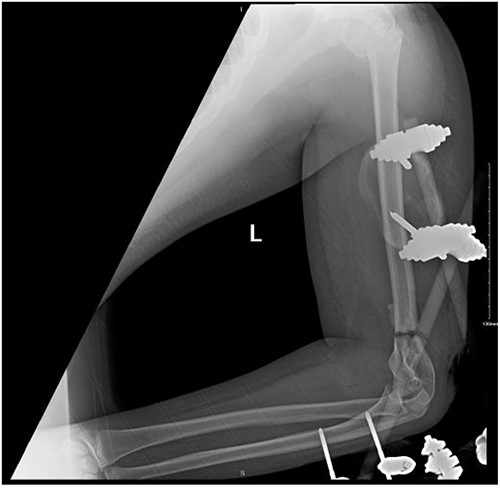

After surgery, the patient was taken back to the ICU and was followed daily by the upper limb orthopedic surgery team for wound care and change of dressings. Four days later, the patient’s condition had improved and he was assessed for distal neurovascular function, which was intact. Afterwards, range of motion was assessed, and no complications were reported before discharge. The patient was kept as an inpatient for almost two more months under the orthopedic trauma team for continuation of management and patient optimization. After discharge, the patient was followed in the orthopedics upper limb and trauma clinic for almost 3 years (Figs 4– 6).

(A). Late follow-up anteroposterior (AP) view of the left elbow after ORIF. (B) Late follow-up lateral view of the left elbow after ORIF.

(A) Late follow-up anteroposterior (AP) view of the left shoulder after ORIF. (B) Late follow-up lateral scapula (Y- view) view of the left shoulder after ORIF.

(A) Late follow-up internal oblique view of the left elbow after ORIF. (B) Late follow-up external oblique view of the left elbow after ORIF.

Our patient was followed afterwards for three years with serial x-rays. No signs of growth arrest or deformity due to our surgical intervention were noted. Instead, on follow up, our patient had a functional range of motion. Elbow range of motion was documented to be 30° extension to almost full flexion and intact pronation and supination. The range of shoulder motion was documented as full. Good healing was observed, but there was some hardware prominence that slightly affected the range of motion, and the patient will be booked for hardware removal. The patient was happy and satisfied about the overall outcome and restored functionality.